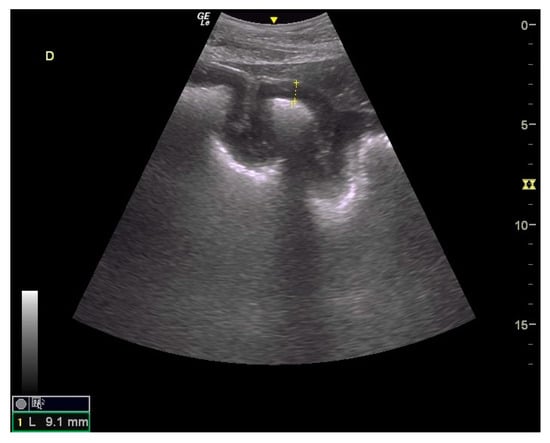

Figure 6.

Ultrasound images of large colon. Moderate to marked thickening of large colon with easily visible villosities; the yellow dote line indicates a measurement of the colon wall at 9.1 mm.

Thickening of the colon wall was significantly greater (p = 0.02) among the horses which did not survive (36 ± 19 mm versus 19 ± 6 mm) (Figure 5). Beyond 22 mm of thickness, the horses presenting such damages of the colon had significantly (p = 0.01) lower chances of survive with a positive predictive value of non-survival of 89% (Table 1). Thickening of the small intestine was observed for 35% (6/17) of the horses on which ultrasonography was performed. Abdominal ultrasonography showed severe thickening of the colon wall with values rarely encountered in other diseases with an average of 29 ± 17 mm (Figure 6 and Figure 7).

Older age, signs of shock (HR, hematocrit, blood lactates, blood creatinine), hemorrhagic diarrhea, ileus, and increased colon wall thickness at the transabdominal ultrasonography exam were associated with non-survival and may help practitioners assess prognosis. Using a threshold of hematocrit > 60%, blood lactate > 4.5 mmol/L, creatinine > 229.8 μmol/L, and colon wall thickness > 22 mm places the positive predictive value for non-survival above 89% for each variable.